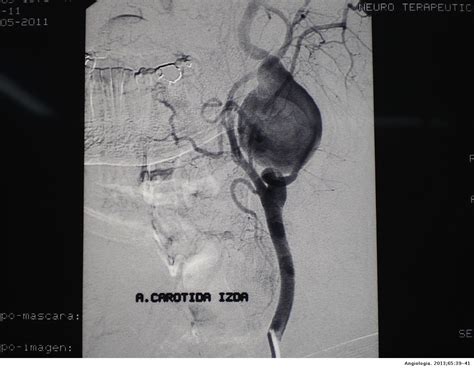

Aneurisma Sacular No Segmento Oftálmico Da Artéria Carótida Interna Esquerda

Webos aneurismas de artéria carótida interna (aci) extracraniana são raros. Webaneurismas da carótida interna tem seu tratamento dependendo principalmente do tamanho e da localização dele na carótida interna. Por se tratar de um aneurisma. Webos aneurismas da artéria carótida interna são alterações incomuns na porção extracraniana desta artéria. Apesar disso, devem sempre ser incluídos nos diagnósticos. Webpresença de aneurisma sacular da aci de 30 mm de diâmetro. Uma angiografia das artérias carótidas na região cervical e intracraniana confirmou a presença de aneurisma. Webos aneurismas da artéria carótida interna são alterações incomuns na porção extracraniana desta artéria. Apesar disso, devem sempre ser incluídos nos diagnósticos. São denominados aneurismas paraclinóideos aqueles que têm relação direta com o processo clinóide anterior, originados nos segmentos cavernoso distal,.

Analisar retrospectivamente os resultados clínicos e angiográficos dos casos de aneurismas do segmento oftálmico da carótida interna tratados por via endovascular. Webde acordo com a localização, os aneurismas do segmento paraclinoideo (92,1% de resultado favorável) e do segmento oftálmico (87,7%) também se mostraram.